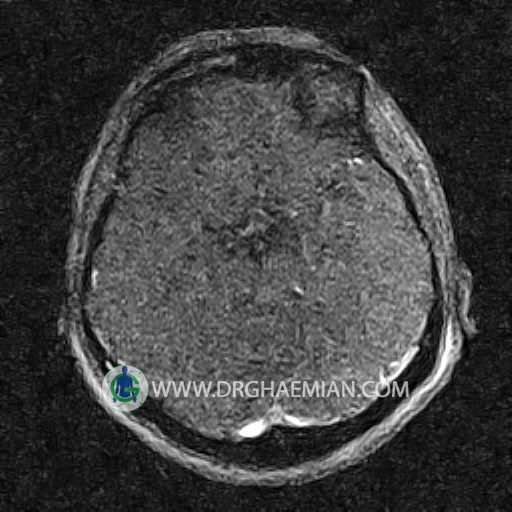

ام آر وی یک روش تصویربرداری دقیق و غیر تهاجمی است که برای معاینه ورید های بدن و ارزیابی سلامت رگ ها استفاده می شود. ورید ها خون را از اعضای بدن به قلب باز می گرداند تا دوباره اکسیژن و مواد مغذی به خون داده شود. ام آر وی جریان خون را ارزیابی و موارد غیرعادی مضر مانند لخته های خونی را شناسایی می کند. در این کیس ترومبوز دیواری مغز در سینوس عرضی راست و ترمبوز جزئی در سینوس عرضی چپ دیده می شود.

Images of the venous cranial vessels demonstrates a superior sagittal sinus of normal caliber with normal arrangement of draining superficial cerebral veins.

The great cerebral vein Galen inferior sagittal , straight sinus and left sigmoid sinus appear normal.

The right sigmoid sinus present a normal caliber.

The other evaluable deep cerebral veins , basal and labbe are normally developed and patent.

The other evaluable portions of the neurocranium show no abnormalities.

– Narrowing of left transverse sinus with filling defect & inthimal irregularity

suggestive for partial thrombosis

– Inthimal irregularity in anterior wall of right transverse sinus suggestive for mural thrombosis

are seen